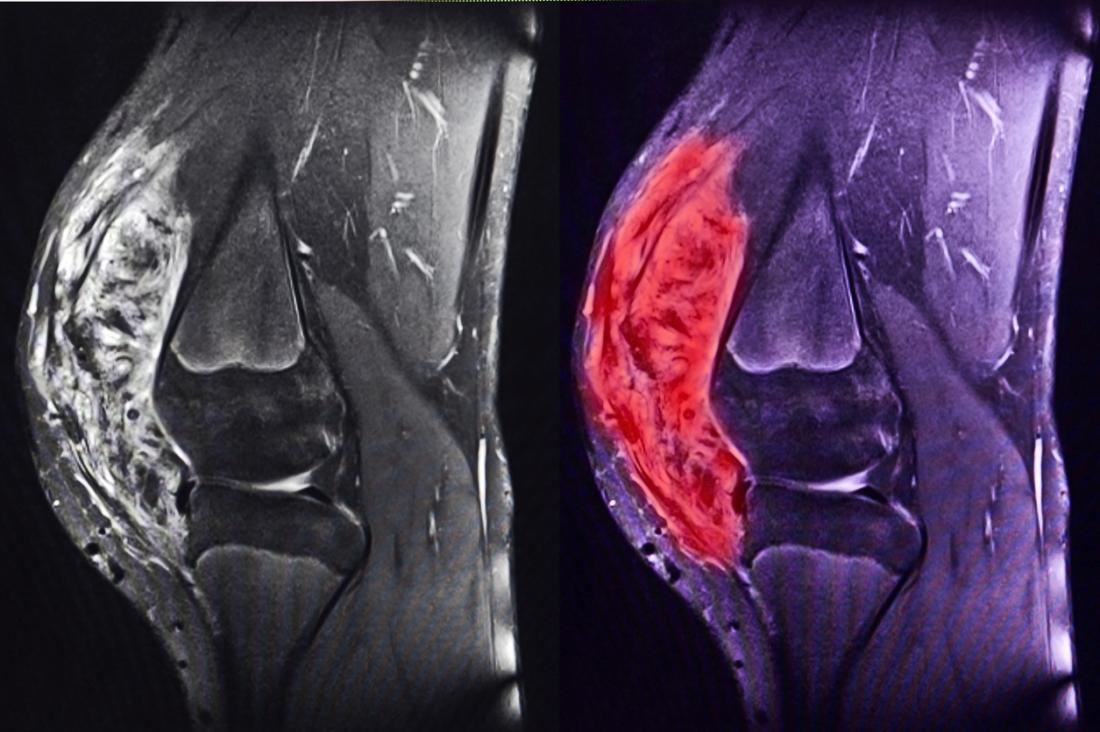

Для диагностики саркомы колена используются методы визуализации, такие как рентген, МРТ и КТ, а также биопсия для подтверждения злокачественного характера образования. Лечение саркомы колена зависит от стадии заболевания и может включать хирургическое вмешательство, химиотерапию и радиотерапию. Врачи подчеркивают важность комплексного подхода и индивидуального выбора методов лечения для каждого пациента, что значительно повышает шансы на успешное выздоровление.

• магнитно-резонансная томография (МРТ).

Саркома колена на МРТ снимке